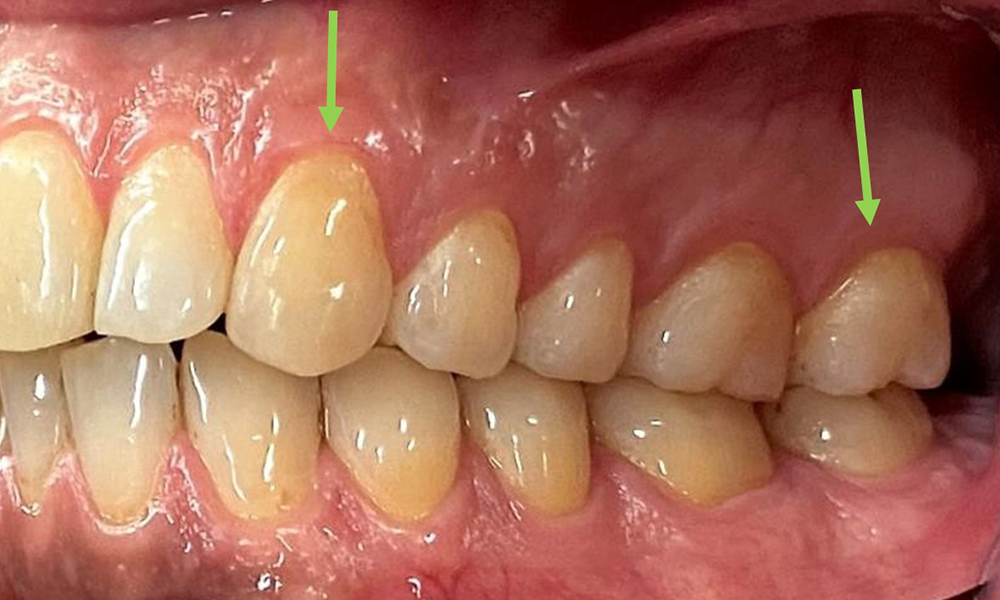

At 1 to 3 mm, the clinical probing depths were within the physiological range. Maxillary recessions of up to 1 mm were observed from 13 to 16 and 23 to 27. The BOP was 15%.

The periodontal status should be thoroughly examined once a year. The detection of plaque using a staining agent may be a source of motivation. The assessment of intraoral findings, buccal surfaces and lingual mucosa are particularly important in smokers, as they will facilitate the detection of any pathological changes at an early stage (6). Photographic documentation allows the assessment of the development of potential pathological mucosal lesions over time. Referral to a specialist may be required to obtain and test tissue samples. Imaging procedures also support the motivational discussions with the patient. They may allow improvements to be highlighted over the course of subsequent preventive dental appointments.